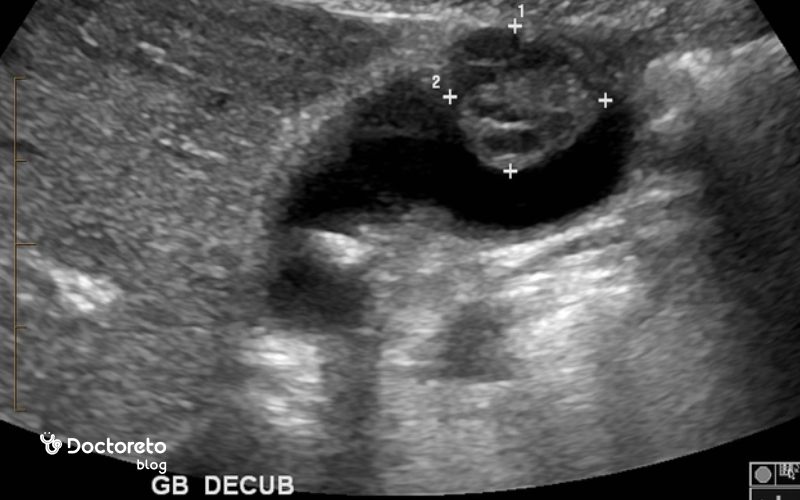

- سونوگرافی شکم: آزمون خط اول برای ارزیابی دیوارهٔ کیسه صفرا، سنگها و اتساع مجاری.

تشخیص سرطان کیسه صفرا ترکیبی از شرححال و معاینه، آزمایشهای خونی و تصویربرداری است تا هم وجود سرطان و هم مرحله و قابلیت جراحیپذیری مشخص شود. تشخیص دشوار است چون در مراحل اولیه علامت واضح ندارد. علائم با بیماریهای شایعتری مثل سنگ صفرا همپوشانی دارند و کیسه صفرا پشت کبد پنهان است. به همین دلیل معمولاً چند آزمون بهصورت همزمان برای تشخیص و مرحلهبندی انجام میشود. روشهای تشخیص به شرح زیر است: